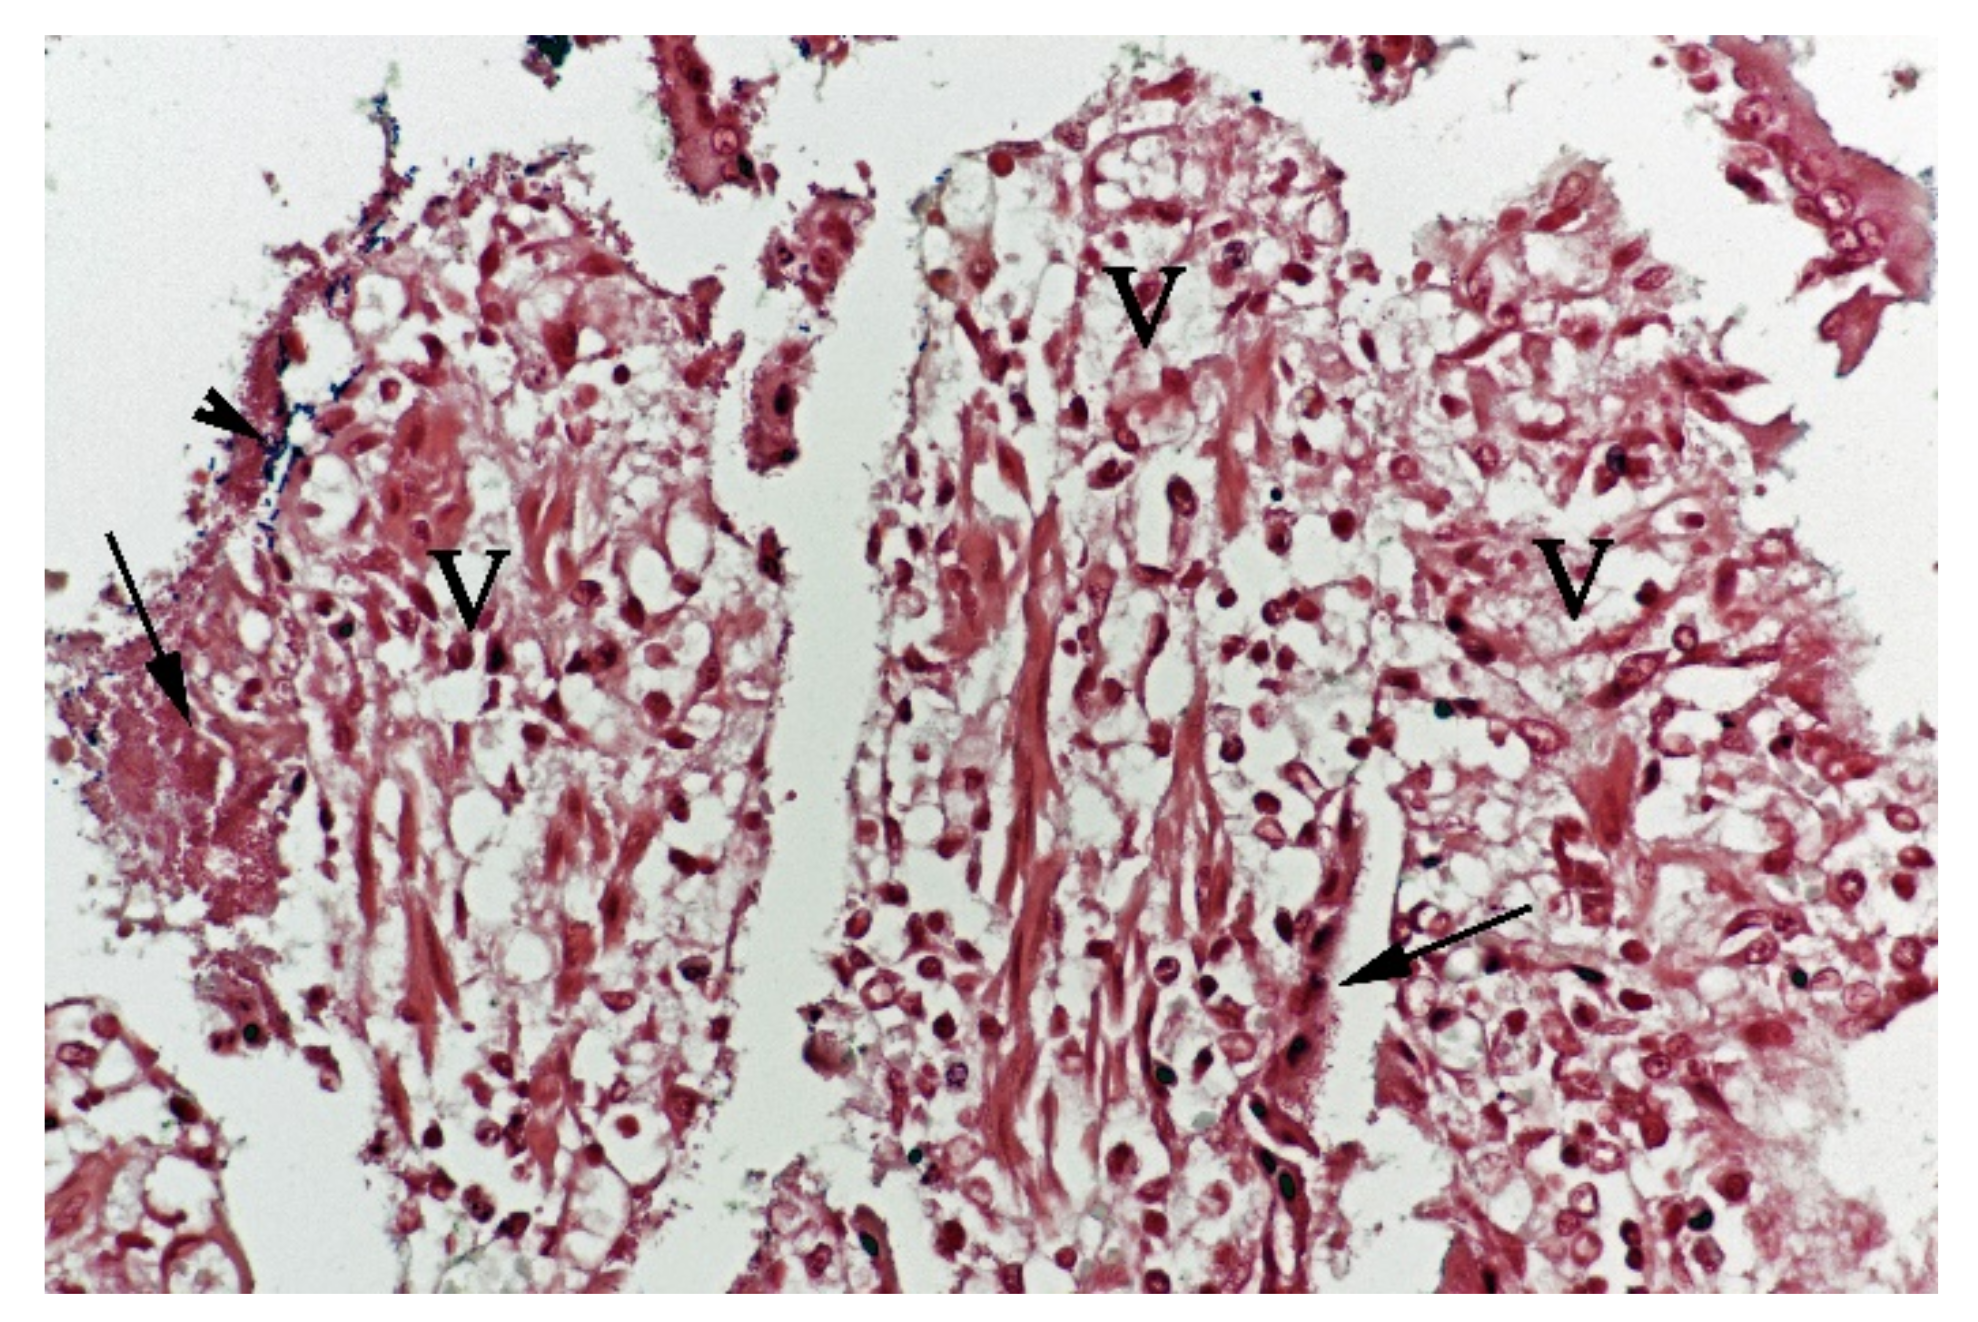

Figure 5.

Histological section from small intestine dog with acute haemorrhagic diarrhoea, Gram-stain. Large amounts of small Gram-negative rods (arrows) were located as single bacteria or thick layers close to the surface of the villi (V). Small amounts of large Gram-positive rods (arrowhead) were present in the clusters of Gram-negative bacteria.

Examination of FISH labelled sections from the stomach, small and large intestine from five of the dogs from which Providencia alcalifaciens had been cultivated, showed that multiple single bacteria and large clusters of small Gram-negative rods were identified as P. alcalifaciens in all examined sections, corresponding to the locations described above for the Gram-negative rods (Figure 6).

Figure 6.

Histological section from small intestine of dog with acute haemorrhagic diarrhoea (a serial section to Figure 5. Providencia alicafaciens was visualised by in situ hybridization using a Cy3 labelled probe. The tissue is orange due to autofluorescence using a red–green double filter set. The Gram-negative bacteria shown in Figure 5 were identified as P. alcalifaciens (P). V = villi.